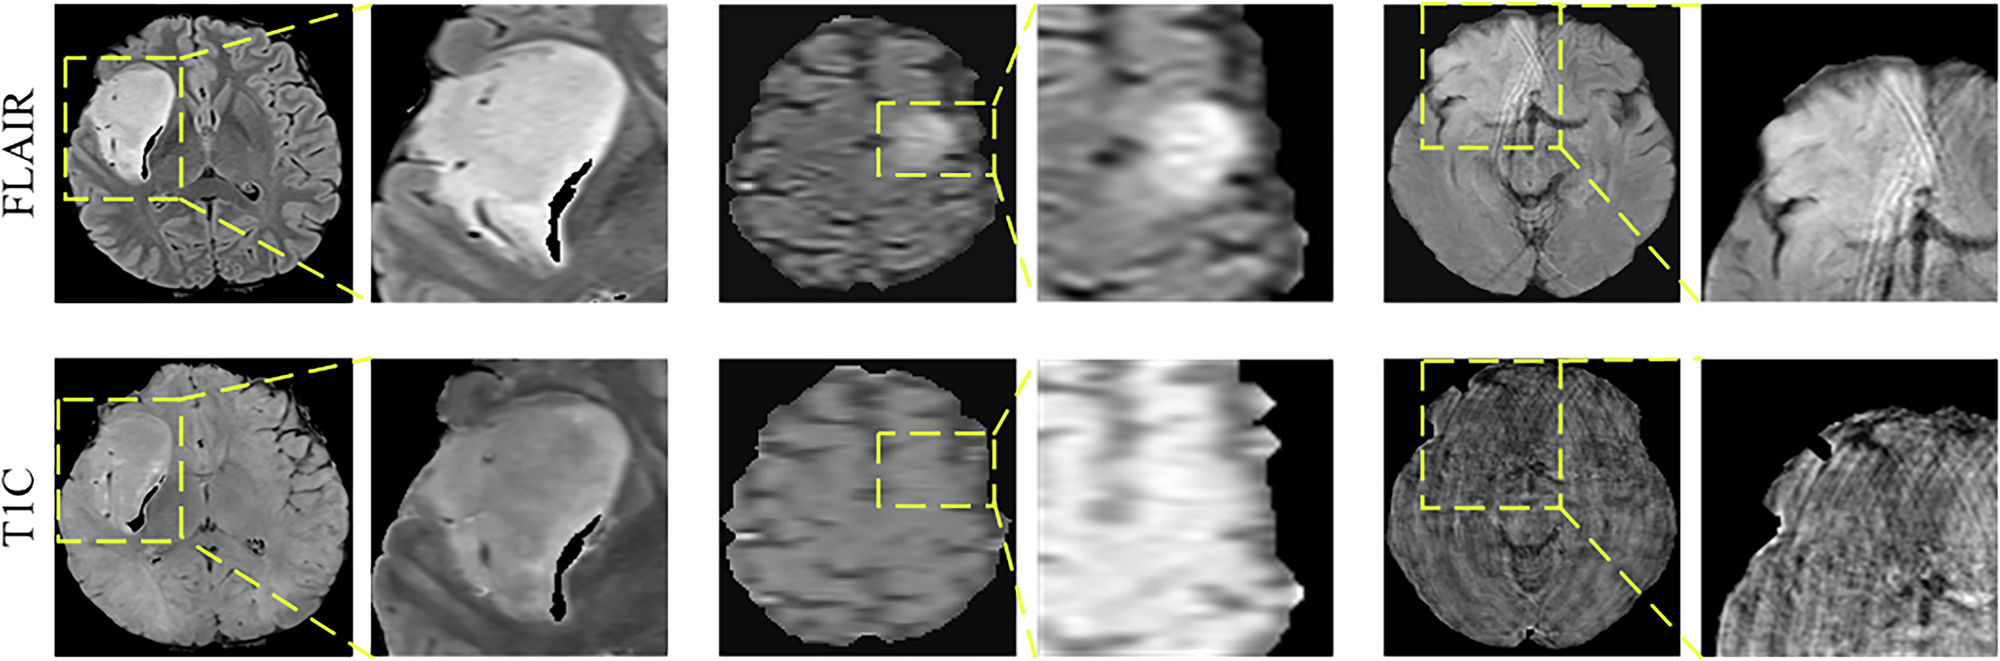

Fig. 13 | npj Precision Oncology